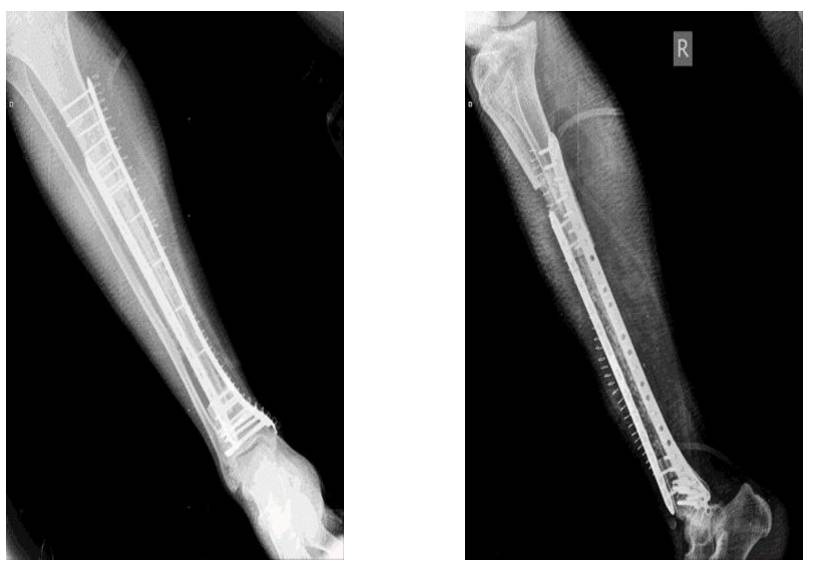

Ameliyat Sonrası: Röntgende fibulanın çift plak ile fiksasyonu görülmekte